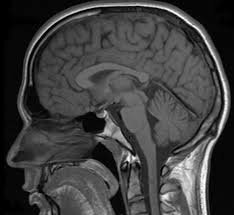

Today we received the CD of Brennan's MRI. We have posted what exactly the doctors found when they did the MRI. Below is what a healthy brain of a 4 year old looks like comparable to what a Chiari brain looks like.

| Healthy Brain of a 4 year old |

| Brennan's brain |

| No cerebral spinal fluid movement.. you can see the part that is falling out |

Sometimes we wonder how he functions. No wonder why the headaches were coming on and still come frequent. He has began to stutter more. January 6th we visit the neurosurgeon.. it can't come fast enough! |